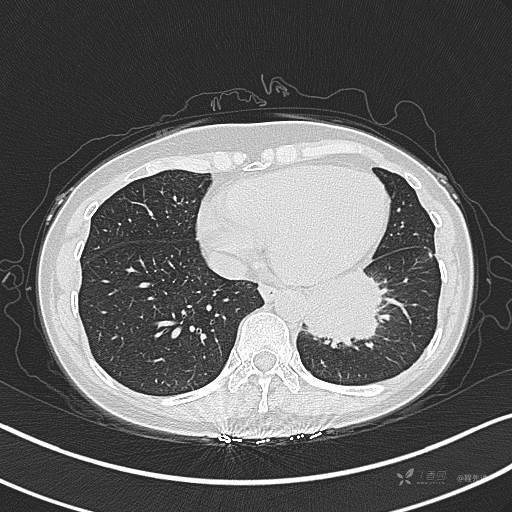

CT平扫

肺窗